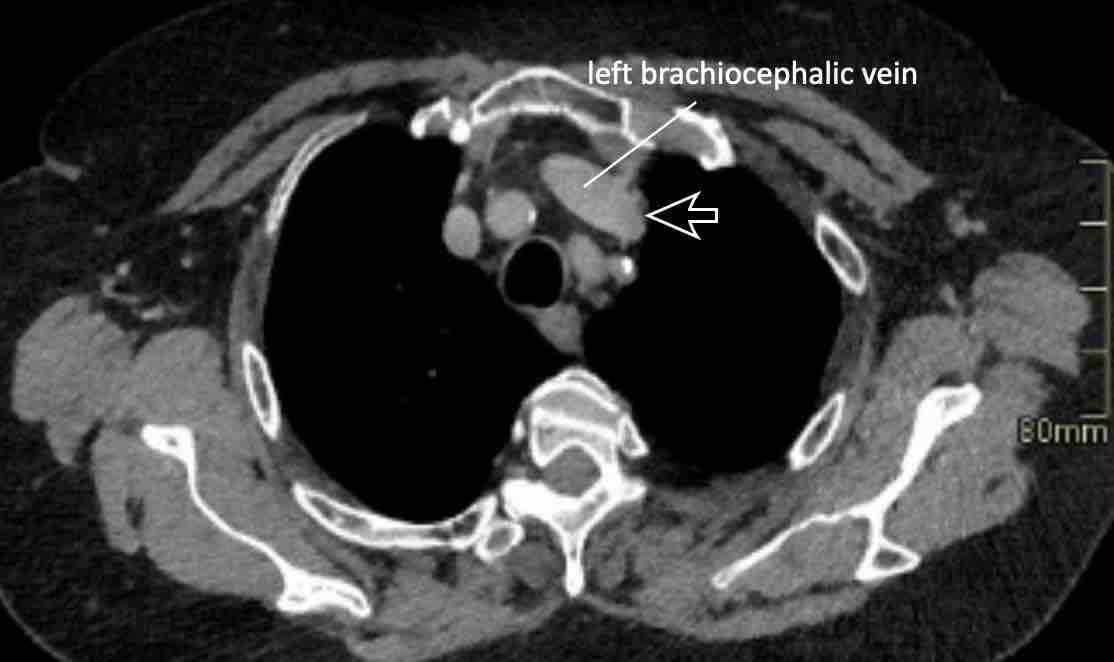

Hình ảnh

Bệnh nhân này được lên kế hoạch cắt thùy trên phải do ung thư phổi và bất thường mạch máu này ban đầu đã bị bỏ sót trên hình ảnh CT.

Những hệ quả trong phẫu thuật của bất thường như vậy nhấn mạnh tầm quan trọng của việc không bỏ sót các biến thể này.

PAPVR bên trái phát hiện tình cờ với dẫn lưu trên tim của máu từ thùy trên trái vào tĩnh mạch tay đầu trái (các mũi tên).